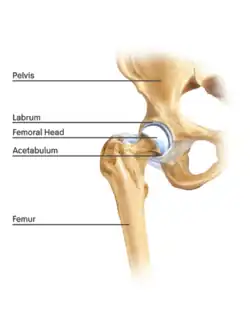

Anatomy

The hip is essentially a ball and socket joint. It consists of the head of the femur (the ball) and the acetabulum (the socket). Both the ball and socket are congruous and covered with hyaline (or articular) cartilage, which allows smooth, almost frictionless gliding between the two surfaces. The edge of the acetabulum is surrounded by the acetabular labrum, a fibrous structure that envelops the femoral head. (See fig. 1) The labrum acts as a seal, or gasket, around the femoral head. However, this is not its only function, as it has been shown to contain nerve endings, which may cause pain if damaged.[18] The blood supply of the labrum has also been demonstrated.[25] The joint itself is encompassed by a thick, fibrous joint capsule, which is lined by synovium. The ligaments that keep the hip joint in place are in fact, thickened areas of joint capsule, rather than distinct structures. The synovium generates fluid that lubricates the joint; in that fluid are the nutrients needed to keep the cartilage cells alive. A total of 27 muscles cross the hip joint, making it a very deep part of the body for arthroscopic access. This is one reason why hip arthroscopy can be quite technically demanding.

The cartilage lining of the socket is in the shape of an inverted horseshoe. The middle of this is termed the cotyloid fossa. Arising from the cotyloid fossa and connecting to the femoral head lies the ligamentum teres. The function of this in the adult is under debate, but in childhood the ligamentum teres carries a blood vessel from the pelvis to the femoral head. This blood vessel usually becomes redundant with age. Arthroscopic hip surgeons are becoming increasingly convinced that the ligamentum teres acts as an internal stabiliser of the hip joint, and pathological injury to the ligament is now a recognised cause of hip pain and instability.[8][26]